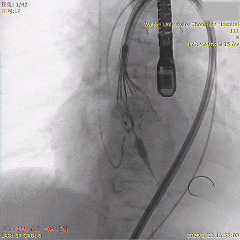

为降低起搏器风险,追求更完美精准植入,选择回收重新定位释放

第二次瓣膜稳定释放

全展开位评估:左右重合体位造影可见无冠窦侧深度约为瓣下1mm

全展开位评估:左冠切线位造影可见左窦侧深度约为瓣下5mm

充分评估后选择脱钩,瓣膜稳定释放,无二次位移